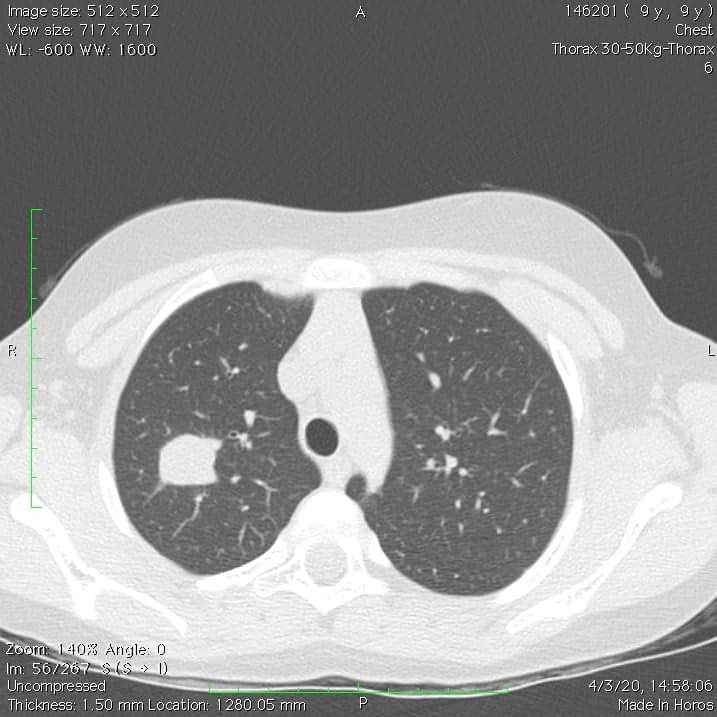

Στην φωτό 1 με βλέπετε με την μικρή 8χρονη πριγκίπισσα Β την ώρα που την παραδίδω στην μητέρα της για εξιτήριο, 24 ώρες μετά την θωρακοσκοπική επέμβαση μέσω της τομής 2 εκατοστών (φωτό 2), για την μάζα στον δεξιό της πνεύμονα (φωτό 3). Στην φωτό 4 βλέπετε το παγωτό που την κέρασα 2 ώρες μετά από το χειρουργείο.

Η μικρή Β βρέθηκε να έχει αυτή τη μάζα στον πνεύμονα σαν τυχαίο εύρημα. Με συνοπτικές διαδικασίες κανονίστηκε η παραπομπή της μέσω του Υπουργείου σε γνωστό ιδιωτικό νοσοκομείο για την διενέργεια θωρακοτομής (φωτό 5), χωρίς καν να υπάρχει πριν βιοψία ή ολοκληρωμένος απεικονιστικός έλεγχος με αξονικές και PET scan. Το “πακέτο ” περιλάμβανε πολυήμερη παραμονή στην μονάδα εντατικής θεραπείας και εξιτήριο μετά περίπου 15 ημέρες…